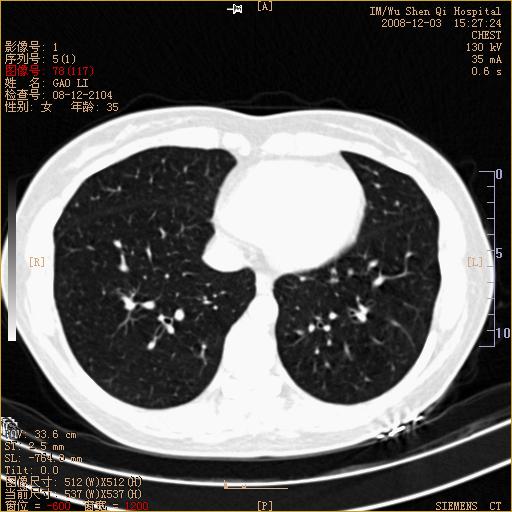

标题: CT16895:女,35岁,反复咳嗽数月,只传部分图像,是否考虑 [打印本页]

标题: CT16895:女,35岁,反复咳嗽数月,只传部分图像,是否考虑

左下肺支扩

典型“印戒征”。

印戒征,支持支扩.

左下肺扩支

印戒征,支扩